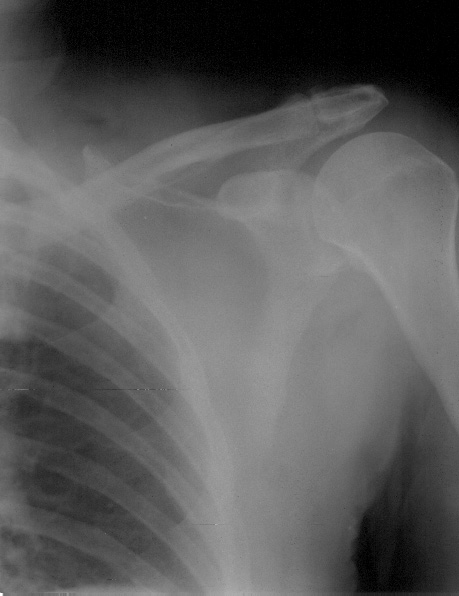

To provide an opportunity for the comparison of image scanning techniques, we are posting in the "Digital Images" forum of the HWB Home Page (http://www.hwbf.org/hwb/) an AP Shoulder film scanned with a $16,000 Howtek Scanmaster DX Xray scanner and a $200 "Snappy" video digitizer. The "Snappy" plugs into the video port of a camcorder or VCR. JPEG compression of either 5:1 or 10:1 are applied to the scans. We would be interested in any feedback with respect to the diagnostic quality of these images.

Click images to enlarge.ROW 1: JPEG 5:1 compression

3)